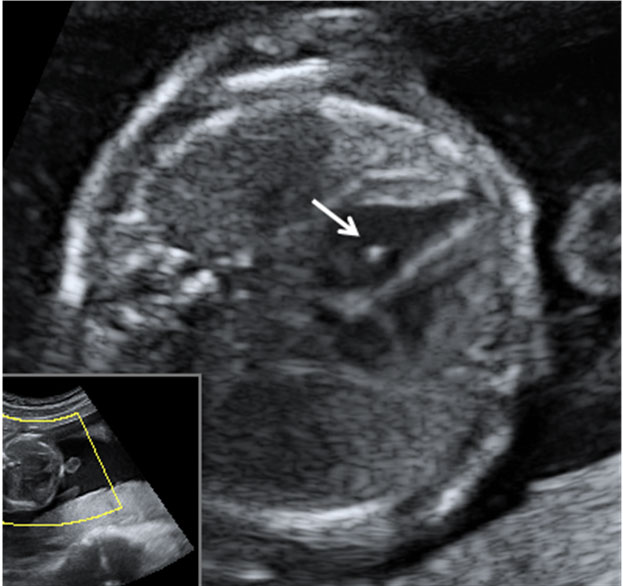

En la imagen ecográfica podemos ver el corte de la cabeza fetal donde se muestra la medición de un ventrículo cerebral aumentado de tamaño (o ventriculomegalia).